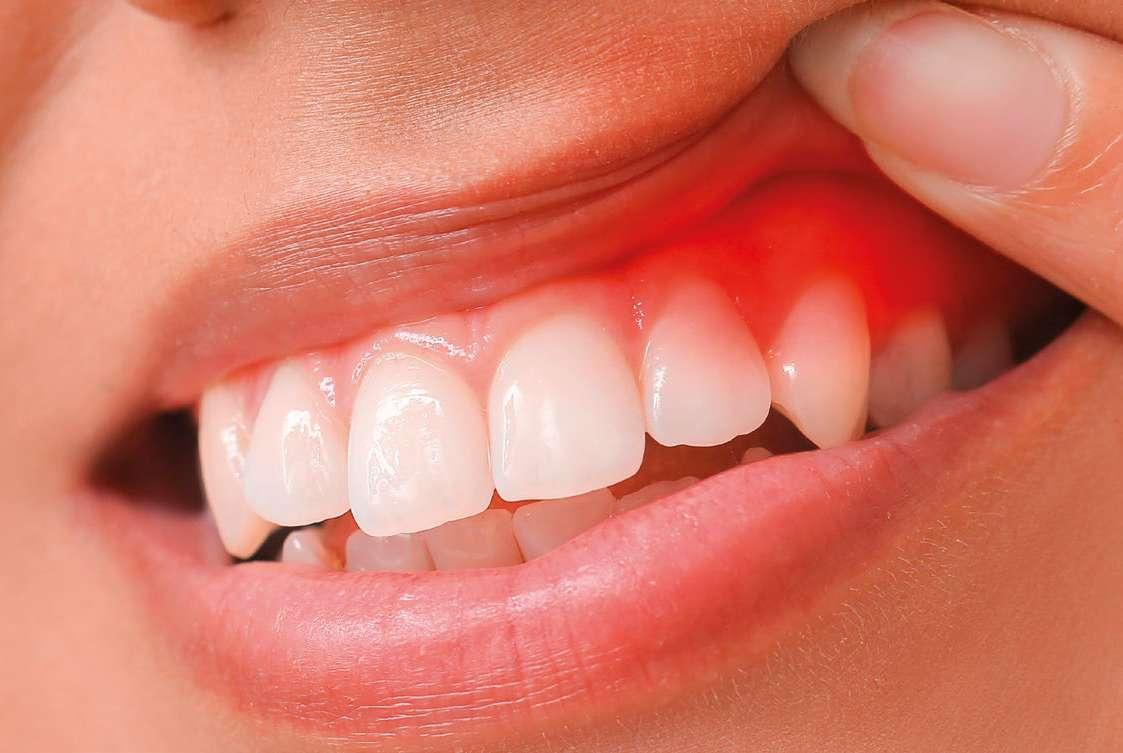

¿Encías inflamadas? No, yo uso

DOS NUEVAS FÓRMULAS PARA

PREVENIR Y TRATAR LA GINGIVITIS

Parogencyl Encías Control y Parogencyl Encías Forte te ayudan en el cuidado de las encías.

La gingivitis o inflamación de las encías es uno de los problemas más frecuentes que puede padecer nuestra boca. Según un estudio de Images en Dermatologie, afecta a 8 de cada 10 adultos a lo largo de su vida. Se refleja en síntomas como la hinchazón o la rojez de las encías, pero también puede llegar a generar sangrados durante el cepillado. Si se trata adecuadamente solo produce molestias temporales, pero, si no se cuida a tiempo, puede llegar a destruir los tejidos gingivales y conducir a enfermedades más graves como la periodontitis, que ataca los tejidos óseos y puede provocar la pérdida de piezas dentales. La causa directa de la gingivitis es la acumulación

de placa dental que se deposita en la superficie de los dientes y las encías. Las bacterias contenidas en la placa dental, si no se eliminan con una adecuada higiene bucal, se combinan con los minerales de nuestra saliva, calcificándose y formando así una capa dura, el sarro, el cual se adhiere a la superficie de los dientes y puede llegar a provocar una infección crónica. Los motivos de esta situación, aparte de una deficiente higiene bucal, pueden ser muy variados como el tabaquismo, la diabetes, la acción de ciertas enfermedades, los efectos secundarios de algunos medicamentos, cambios hormonales, el estrés, deficiencias nutricionales o problemas con prótesis dentales.